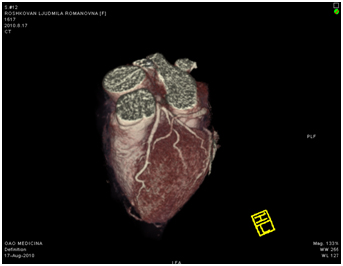

МСКТ коронарных артерий от 08.2010

Ствол ЛКА широкий, имеет ровные контуры, не стенозирован. ПНА в проксимальном сегмента имеет неровные контуры за счет кальцинированных и частично кальцинированных бляшек, просвет артерии на этом уровне сужен до 30-50%, в среднем сегменте определяется ряд пристеночных и циркулярных мягких бляшек, со стенозом артерии до 60-75%, дистальные отделы артерии малого калибра, плохо заполняются контрастным веществом. ОА нормального диаметра, заполняется контрастным веществом без признаков гемодинамически значимого стеноза. ПКА нормального диаметра, в проксимальном сегменте имеются смешанные частично кальцинированные бляшки, стенозирующие просвет до 30%, в среднем сегменте визуализируется пристеночная смешанная бляшка, стенозирующая просвет до 50-70%, дистальный сегмент не изменен. Правый тип коронарного кровоснабжения.

18.08.2011 выполнена селективная коронарная ангиография.

Огибающая коронарная артерия без признаков стенозирующего атеросклероза.

Правая коронарная артерия – в средней трети стеноз 70%. Правый тип коронарного кровообращения.

Передняя межжелудочковая артерия

Правая коронарная артерия